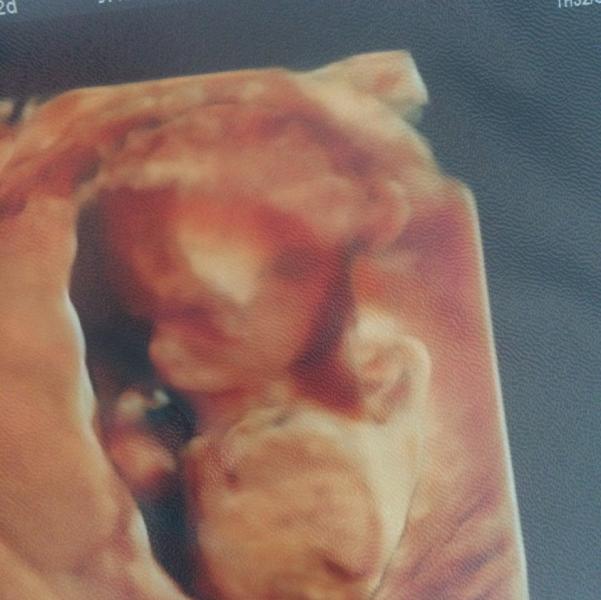

Сходили на узи в Алмиту,все очень понравилось,врач Кучеев В.В. очень добрый и приятный мужчина,все показал и рассказал,ответил на все вопросы. А самое главное у нас будет сын👏🏼 муж на седьмом небе! Я счастлива)